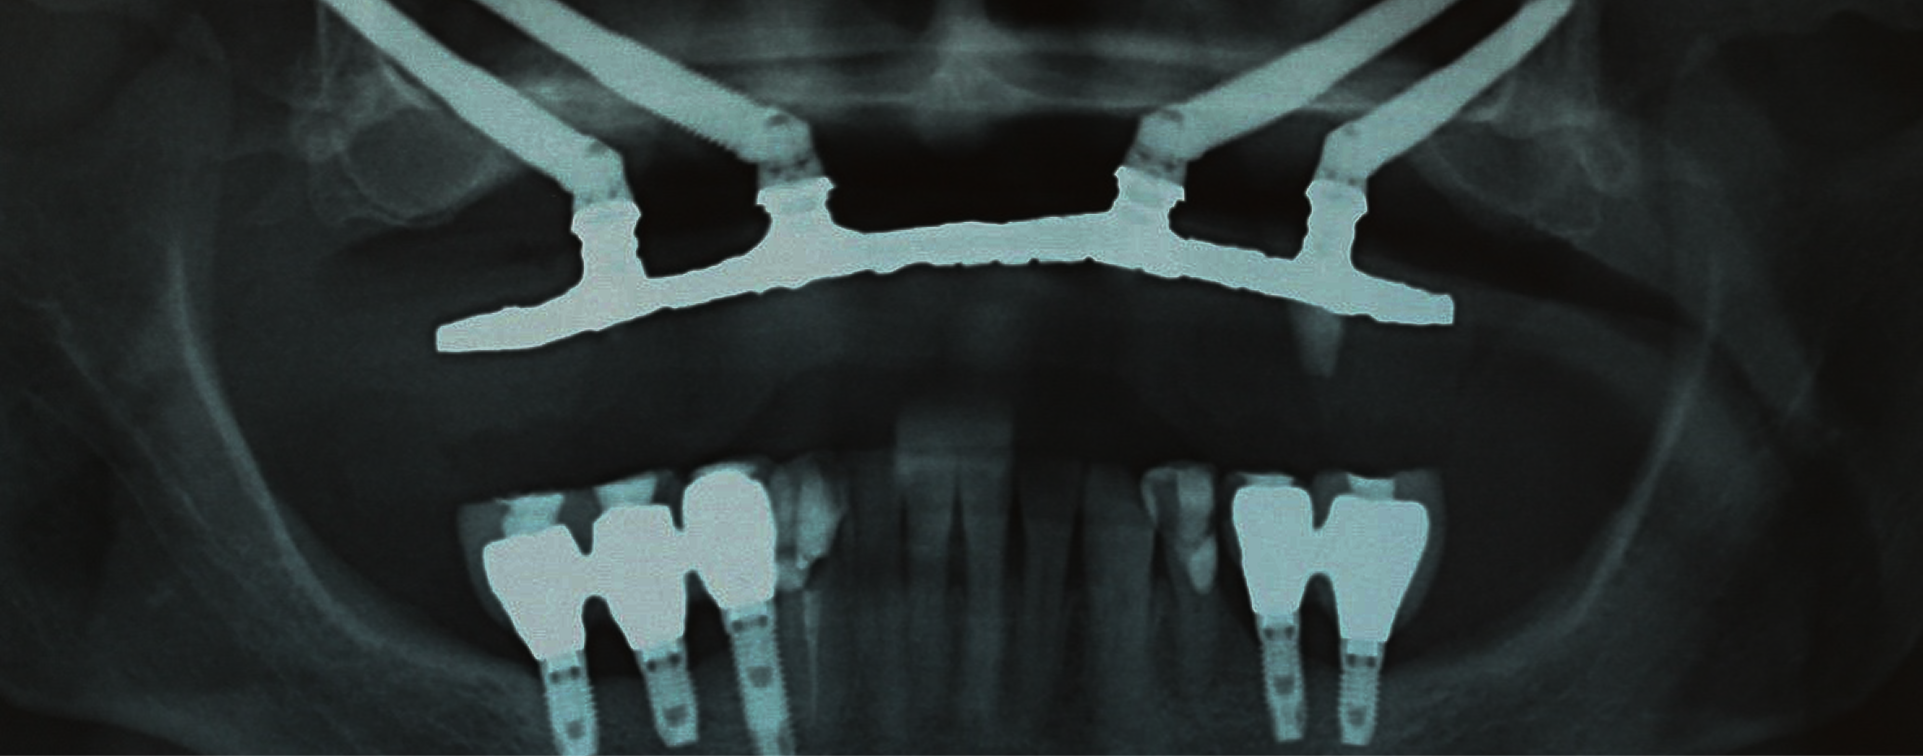

São implantes dentários mais longos (de 30 a 55 mm) que são fixados no osso zigomático (osso da maçã do rosto), em vez do osso maxilar superior tradicional. É uma solução para pacientes que perderam muito osso na maxila superior.